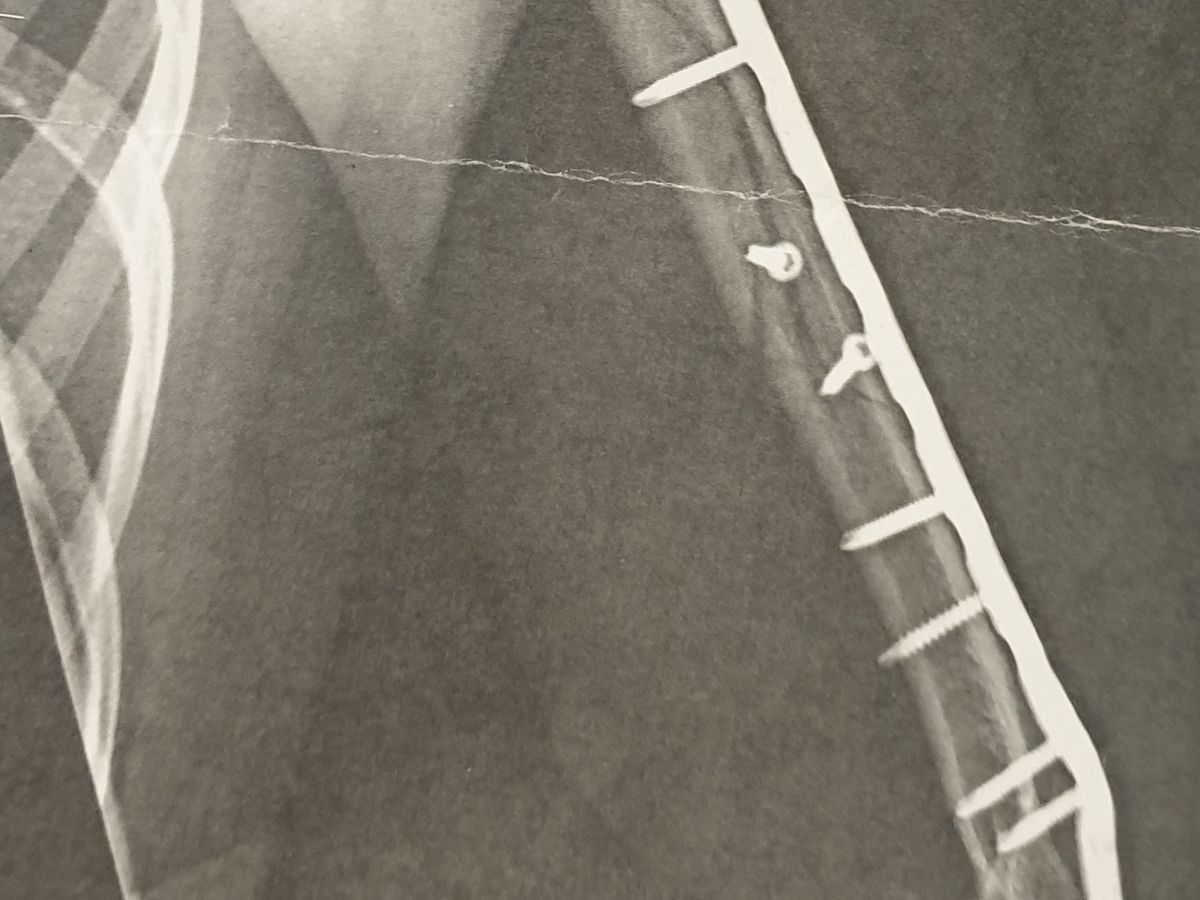

Ich bin Opfer von Polizeibrutalität. Unter sehr banalen Umständen wurde meine Hand von einem Polizisten gebrochen, wie auf dem Bild zu sehen ist. Ich wurde brutal aus der Kirche geworfen, weil ich keinen Ausweis vorweisen konnte. Zwei Wochen nach den Vorfällen wurden alle Vorschriften aufgehoben. Zu dieser Zeit war ich auch arbeitslos.

I am victim of police brutality. In very innocent circumstances my hand was broken by the policeman as seen on the picture. I was bruttaly thrown out of church because I didn`t have covid certificate. After two weeks of the incidents all regulations were lifted. I was also unemployed at that time.